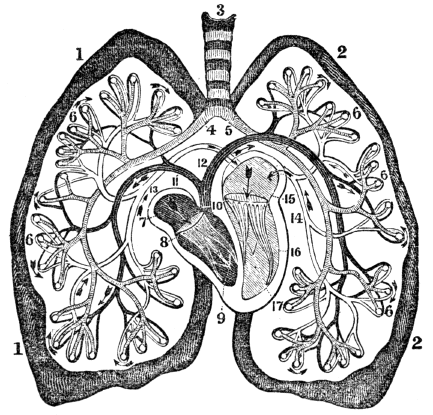

| 23. | Anatomy of the Respiratory Organs, | 209 |

| 24. | Physiology of the Respiratory Organs, | 217 |

| 25. | Hygiene of the Respiratory Organs, | 228 |